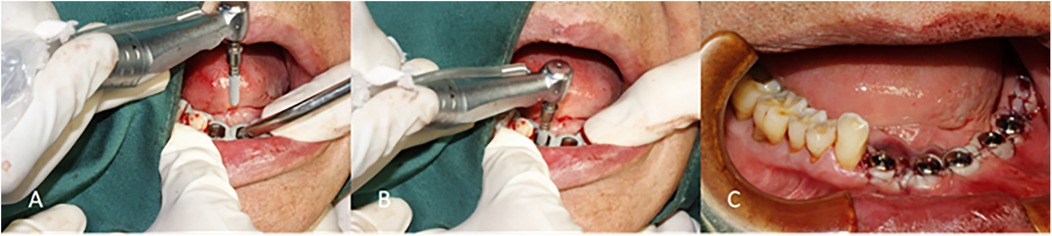

Background: Digital guided implantology improves safety and precision compared to freehand methods. A survey indicated that half-guided templates are more commonly used than full-guided ones in China. This study aims to assess the accuracy of implant placements using half-guided and full-guided digital surgical templates, considering factors like jaw location, tooth position, support type, implant timing, and bone density. Methods: 87 implants (52 half-guided, 35 full-guided) were evaluated by comparing pre-and postoperative CBCT scans to measure deviations in coronal, apical, depth, and angular positions. Bone density was also assessed in relation to the implant deviations. Results: The findings revealed that the half-guided group exhibited significantly greater deviations in several areas: maxillary angular deviations, anterior coronal and depth deviations, posterior depth deviations, tooth-supported guide depth deviations, immediate implant coronal and angular deviations, and delayed implant depth deviations (P < 0.05). No significant differences were noted in other measurements. In the bone density analysis, only the full-guided group showed a significant negative correlation between bone density and apical deviation (P < 0.05). Conclusion: Based on statistical results, power calculations, and subgroup effect sizes, the following clinical recommendations are derived: Half-guided templates, owing to their superior cost-effectiveness in fabrication time and cost, are recommended for use in mandibular posterior regions, mucosa-supported templates, delayed implantations, and clinical scenarios with uneven bone density distribution at implant sites. In contrast, full-guided templates are more suitable for maxillary implantations, anterior regions, tooth-supported templates, immediate implantations, and sites with homogeneous bone density distribution.